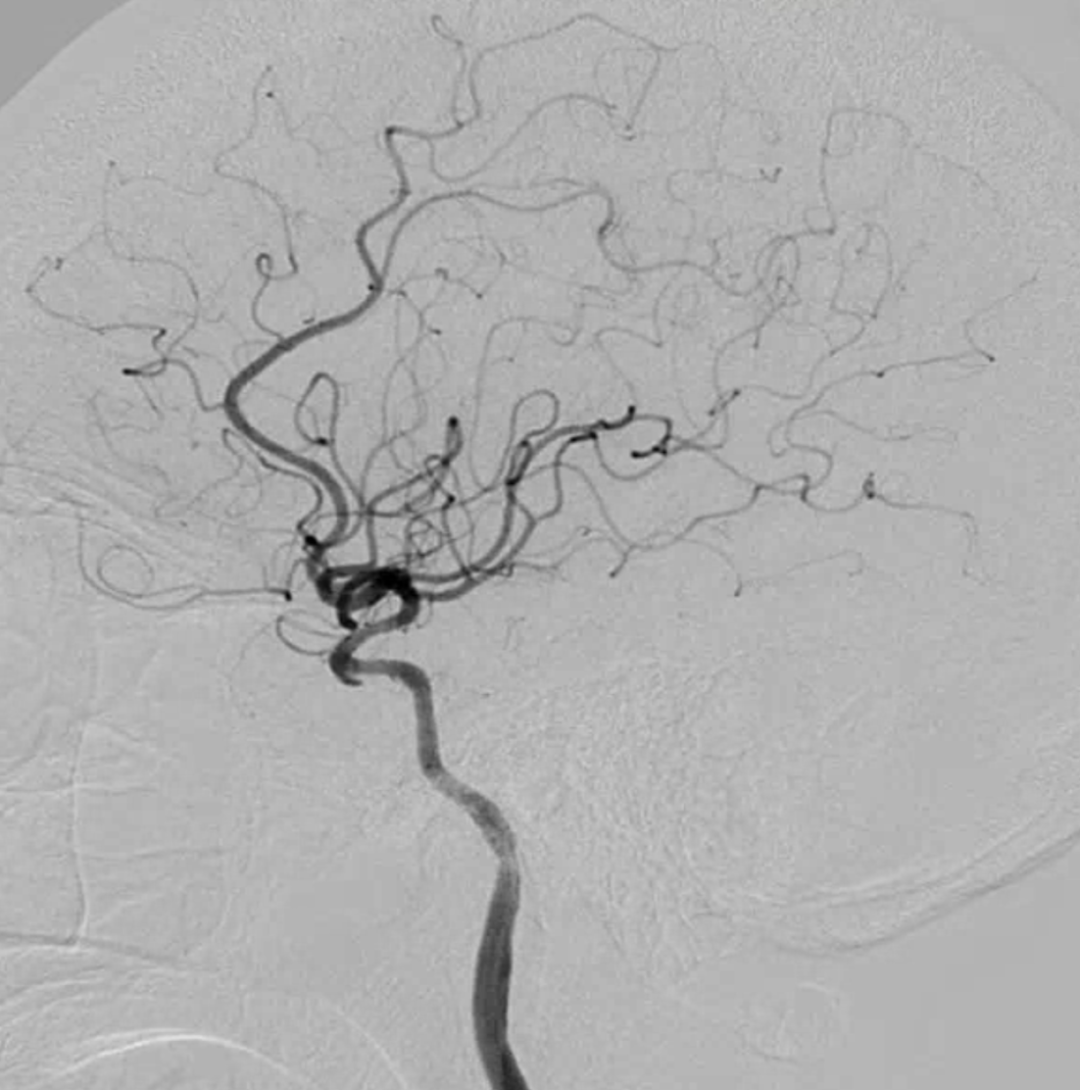

脑血管造影提示右侧颈内动脉颅内段多发动脉瘤(反主动脉弓)

脑血管造影提示右侧颈内动脉颅内段多发动脉瘤

4mm×30mm Streamline

术后4月余随访:多发动脉瘤均未见显影,远端残余轻度狭窄

术前术后对比